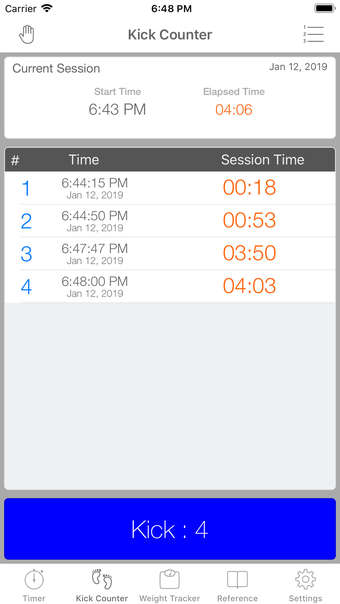

이 어플리케이션은 조기 분만을 겪는 여성들이 분만 과정을 지속적으로 추적할 필요가 있는 경우에 디자인되었습니다. 기능성을 희생하지 않고 사용자 친화적인 어플리케이션을 만들고자 했습니다.

이 어플리케이션은 분만 진행 상황을 명확하게 보여주며, 현재 분만 단계, 이전 및 현재 수축의 시작 및 종료 시간을 보여줍니다. Full Term은 수동으로 각 수축을 시작하고 중지할 필요가 없으며, 어플리케이션을 재시작하더라도 분만 기록을 추적합니다.